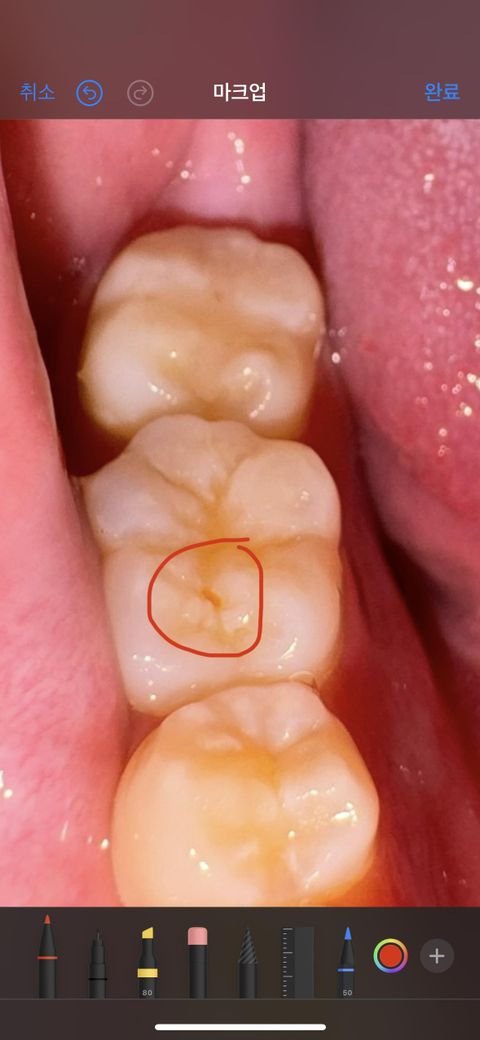

이거 충치 일까요 ㅠㅠ 모르겠습니다 ㅠㅠ

충치일까요 최근에 3달전에 검진가서는 이빨상태 괜찮다고 하셨는데 작은 구멍이 생겨서요 충치인건가요 아니면 다른 것일까요 ㅠㅠㅠ

음식물이 껴잇거나 착색이 됫을 가능성이 있어보이지만 정확한건 치과에 가셔서 검진을 받아보세요.

사진으로 봤을 경우에는 정확한 확인이 어려워 보입니다. 정확한 확인을 위해서는 치근단 사진이나 촉진 등이 필요할 것으로 생각됩니다. 자세한 확인을 위해서 치과에서 진료를 받아보는 것을 권유 드립니다.

충치보다는 치아가 부분적으로 마모된 것 같습니다만 사진만으로는 명확히 판단하긴 어렵습니다.

이전에 떼운 재료 또는 치아가 조금 파절이 있는 것 같습니다 원인이 충치인지는 명확히 알 순 없습니다만 구멍이 있으므로 떼워주는 것이 좋습니다